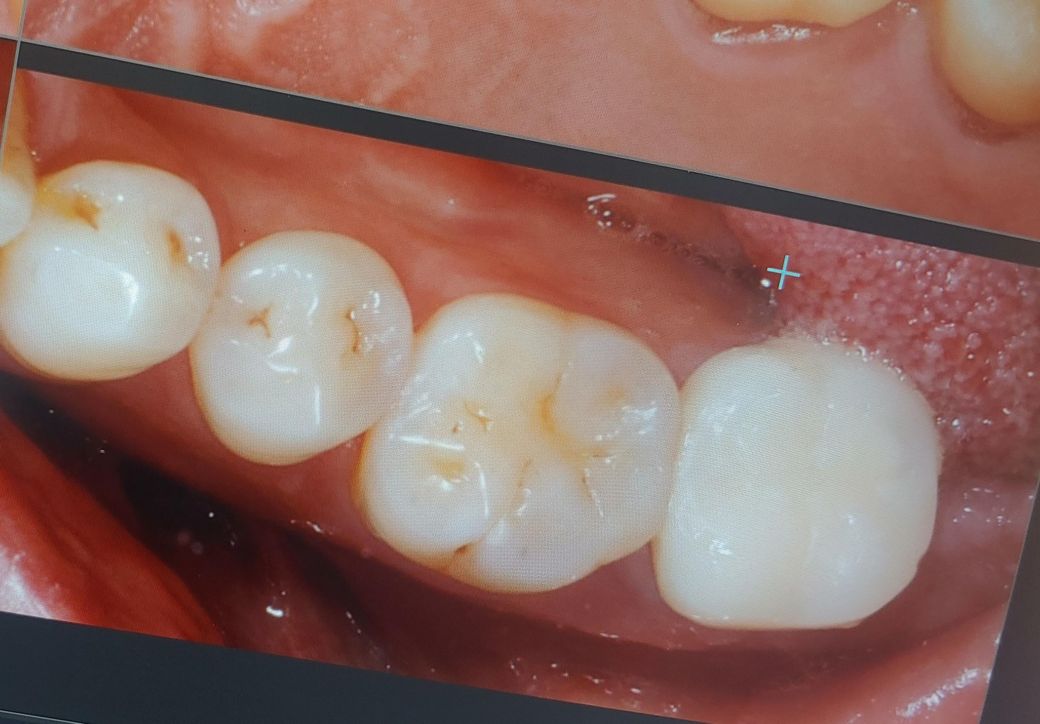

왼쪽 맨끝 어금니 위.아래 치아가 살짝 틀어져 있어서 씹을때 불편한데요.아래 치아는 사진처럼 임시치아 상태구요.맞닿는 위 치아는 교합 문제로 좋지 않은 상태입니다. 위아래 치아 크라운을 해야할 경우 깍은 다음 정상적인 방향대로 크라운을 할 수 있나요? 아니면 교정을 통해 뿌리를 정상적인 위치로 한다음에 정상적인 방향으로 크라운을 해야 하나요?

이정도 각도면 치아 추가 삭제 후 각도를 맞춰 크라운을 진행하는 것도 좋을 것 같습니다. 교정보다 더 단기간에 치료 끝납니다.